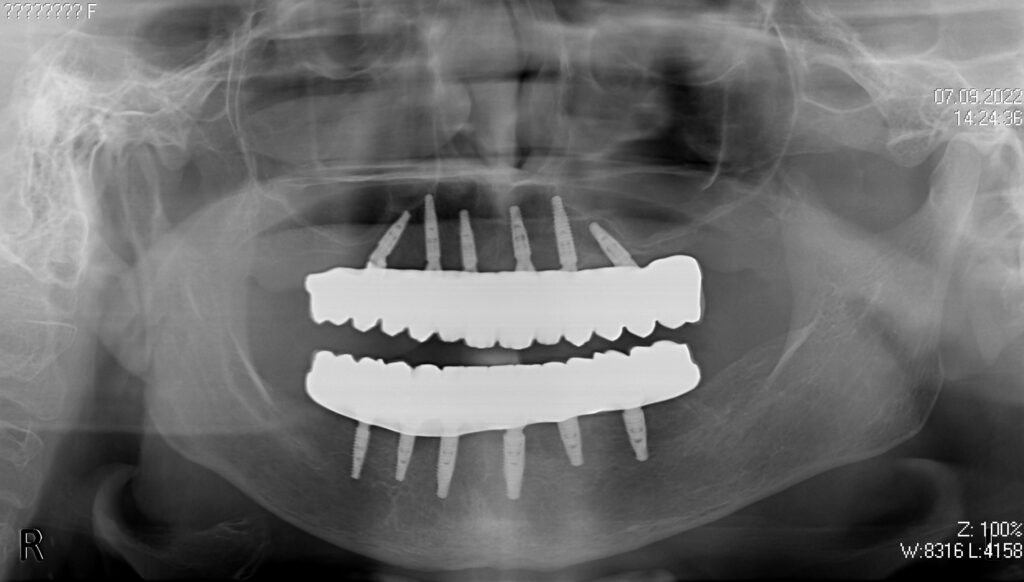

Пациент продолжает лечение спустя 6 месяцев после имплантации и установки временных металлоакриловых протезов с опорой на 6-ти дентальных имплантантах на каждой челюсти.

Диагноз: Полная адентия нижней и верхней челюстей.

снимок

работы врача